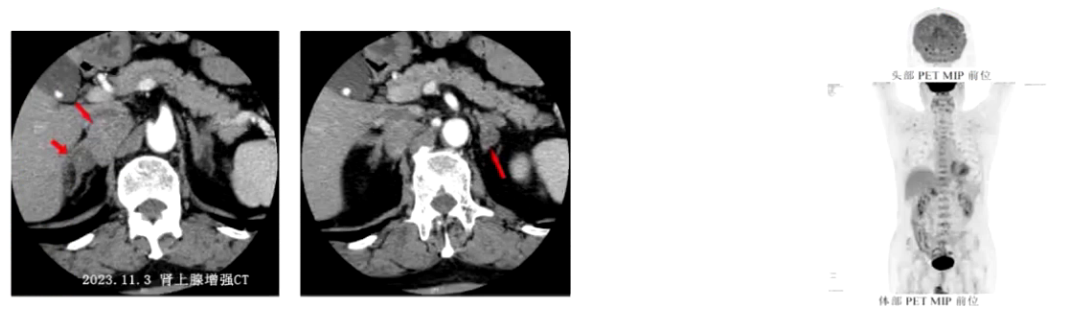

1) 病因探寻:患者此次血压波动,既往原发性醛固酮增多症诊断明确。血儿茶酚胺提示甲氧基去甲肾上腺素2026.6pmol/L、甲氧基肾上腺素792.6pmol/L,均超过参考范围。肾上腺CT提示右侧肾上腺内侧下腔静脉与右侧膈肌之间肿块影4.3cm×2.6cm,考虑神经源性肿瘤,原有双侧肾上腺多发腺瘤仍存在。PET-CT检查提示双侧肾上腺多发低密度结节,部分代谢活性增高,为功能性腺瘤,右侧膈肌角旁代谢活性增高的软组织密度肿块性质待定,不完全除外低度恶性肿瘤可能。结合患者右侧膈肌脚旁占位逐年增大、体重减轻、周围循环充盈欠佳、体位性低血压、血尿儿茶酚胺指标升高,考虑副神经节瘤为此次病情变化主要原因。

3) 临床表现:患者可能出现阵发性血压升高,或持续性血压升高基础上阵发性加重,部分高血压与低血压交替发生,可出现头痛、心悸、大汗三联征,体型大多消瘦。CT或核磁显示密度不均的圆形或类圆形密度影,肿瘤内常有出血坏死或钙化,瘤体可被造影剂增强,转移性瘤体较大,密度不均,外形不规则,可有周围组织浸润。可总结为“6H”,即头痛、心悸、多汗、高血压、高代谢状态、高血糖,本病例患者有头痛、心率增快(心悸表现)、高血压体现,但因症状无特异性,既往未被发现。

4) 分期标准:目前采用ACC的肿瘤分期标准,即传统的TNM分期。T分为T1期(肿瘤最大径<5cm,无肾上腺外浸润)、T2期(肿瘤≥5cm或任何大小无瘤外或肾上腺外浸润的交感神经副神经节瘤)、T3期(侵入周围组织或器官的任何大小肿瘤);N指淋巴结转移,分为无淋巴结转移和有局部淋巴结转移;远处转移分为M0(无远处转移)、M1a(远处转移到骨)、M1b(远处转移到淋巴结、肝或肺)、M1c(骨和多个其他部位的远处转移)。结合本病例患者影像评估结果,考虑目前为T2期肿瘤。